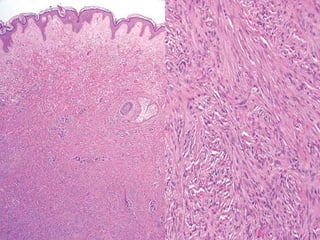

Dermatofibrosarcoma Protuberante

 Es un fibrosarcoma primario bien

diferenciado de la piel.

 Crecimiento lento, localmente agresivo, rara

vez metastatizan.

 Clínicamente son unos nódulos sólidos firmes

que se originan mas frecuentemente en el

tronco.